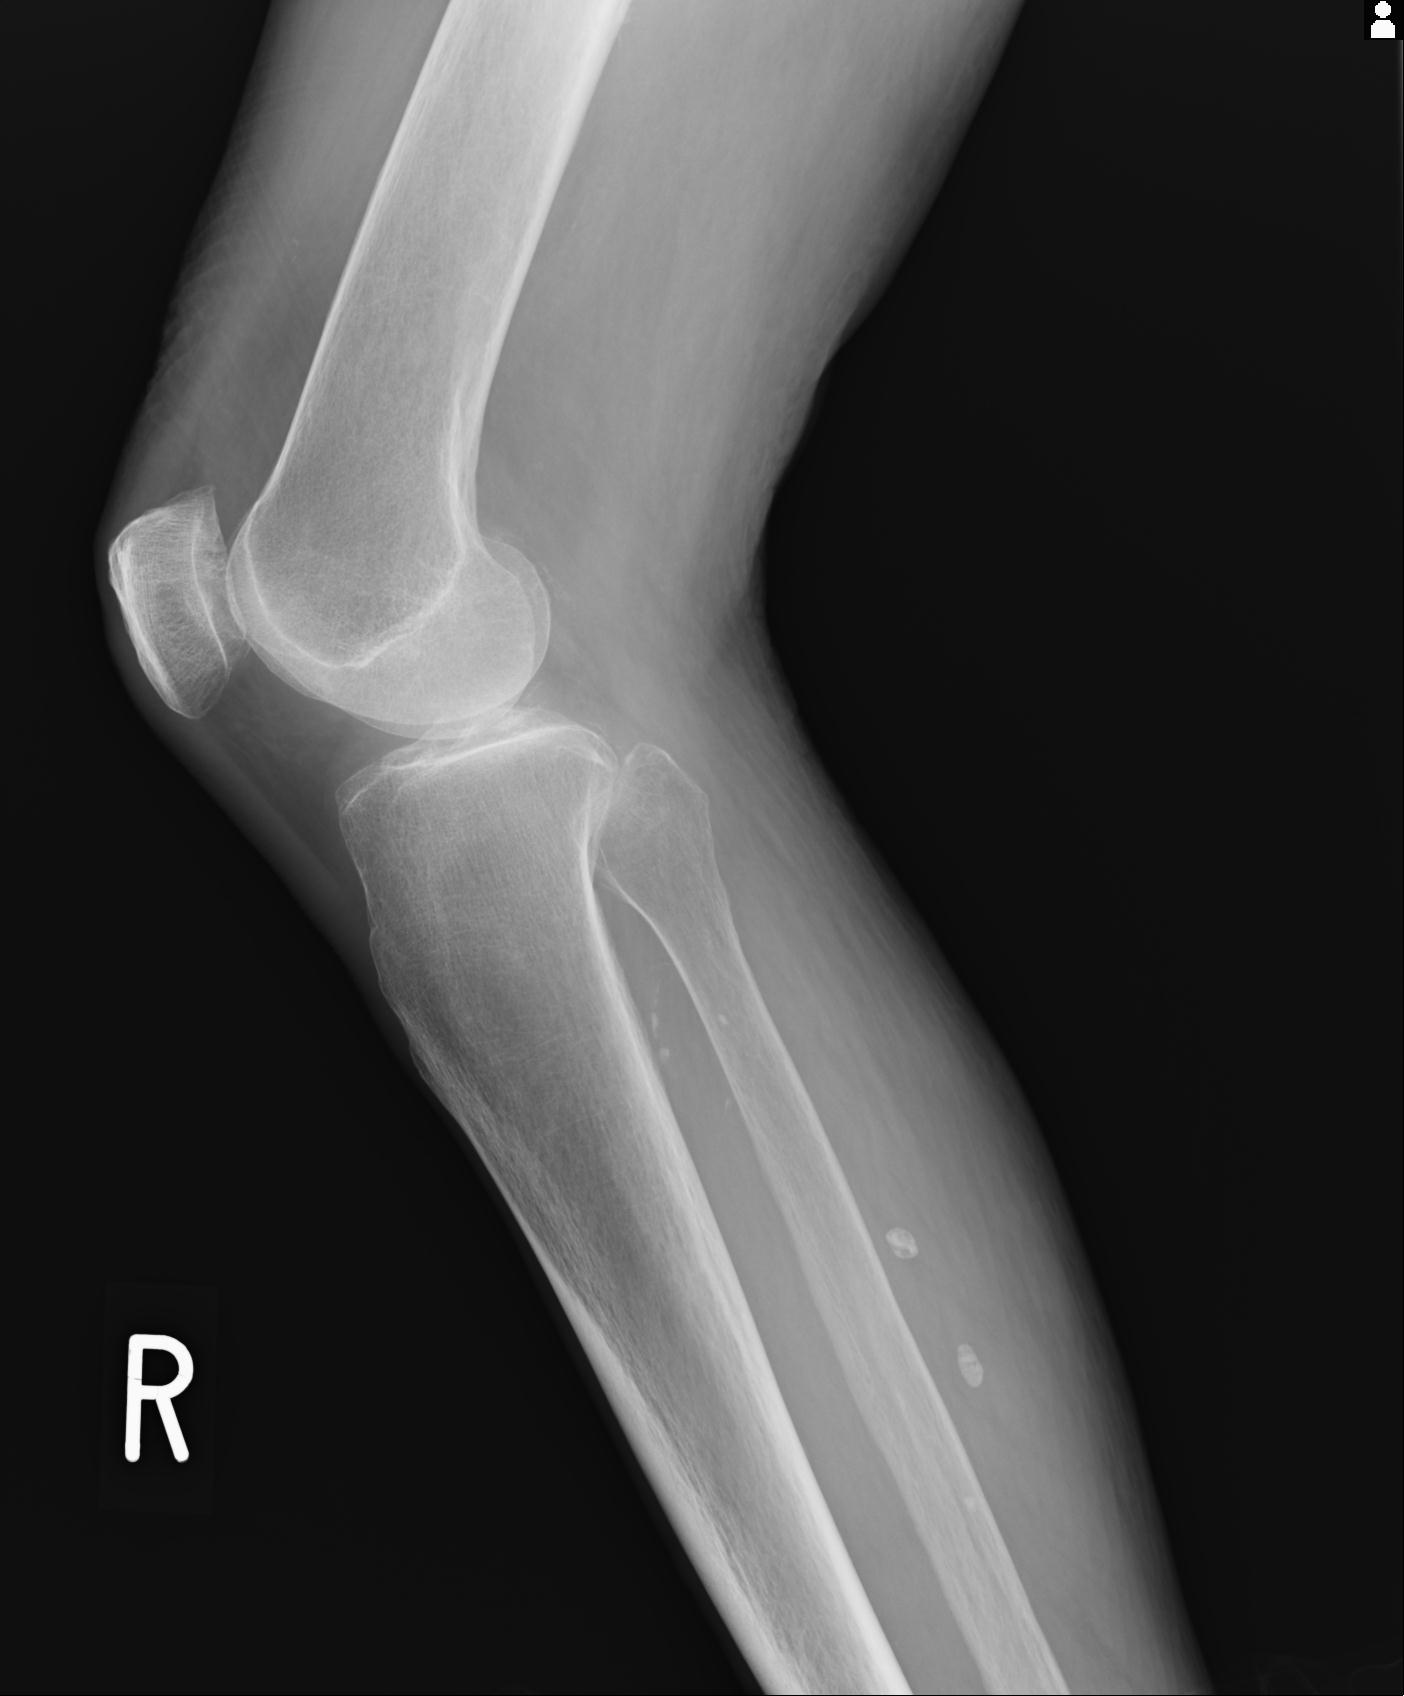

49554 3/13 膝 4R 3/16 4R 1/18 2R 78歳男性 膝蓋骨骨折

100612 11/25 1/20 右膝 2R 84歳女性 右TKA

91983 11/16 左膝 2R 11/18 2R 55歳男性 脛骨骨切り術